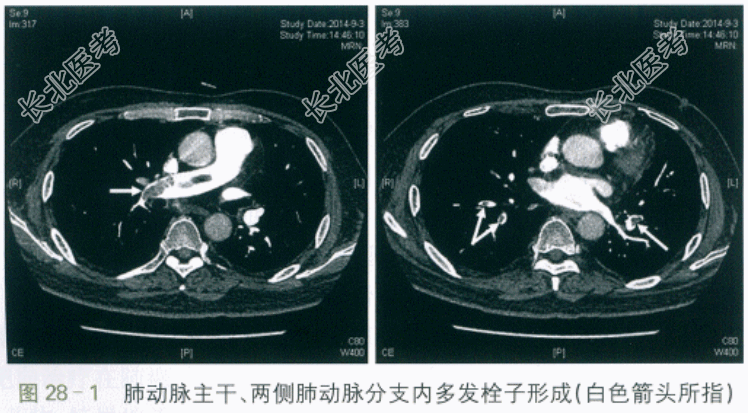

患者,男性,52岁。因"右下肢肿胀10余天,胸闷1周伴痰血"入院。患者10余天前出现右下肢肿胀,较左侧增粗,非凹陷性,表面皮肤无皮疹、破溃,未予重视。1周前自感胸闷,伴痰中带血3次,无发热、胸痛、呼吸困难、心悸等。2天前自感胸闷加重,遂至我院门诊就诊。查血常规:WBC9.93×10⁹/L,Hb129g/L,PLT128×10⁹/L。X线胸片示:两肺未见活动性病变。D-二聚体:15.78mg/L。进一步行CT肺动脉造影示:肺动脉主干、两侧肺动脉分支内多发栓子形成。遂予以收治入院。

CT肺动脉造影示:肺动脉主干、两侧肺动脉分支内多发栓子形成(见图28-1)。